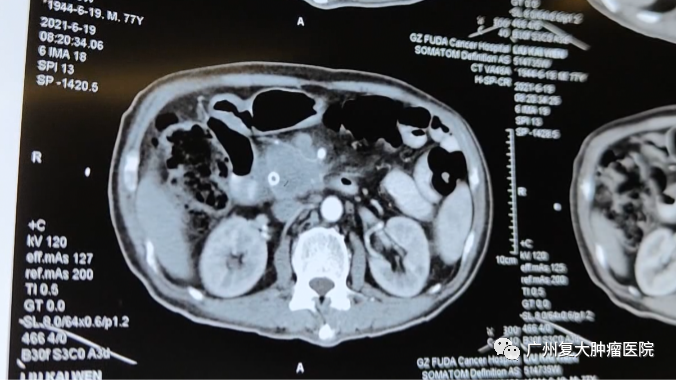

CT圖片

為求進(jìn)一步治療,劉叔來(lái)到我院就診。入院后劉叔完善相關(guān)檢查,其彩超檢查顯示胰頭部有大小約5.1×4.9×3.0cm低回聲腫物、肝臟多發(fā)轉(zhuǎn)移瘤。由于胰頭腫物不僅累及相鄰門(mén)靜脈并壓迫膽總管下端致膽總管、肝總管、膽囊管及肝內(nèi)外膽管擴(kuò)張,還浸潤(rùn)周?chē)鹃g隙,胰腺體尾部萎縮;同時(shí)檢查發(fā)現(xiàn)劉叔存在輕微房顫的癥狀,無(wú)法實(shí)行根治性手術(shù)。